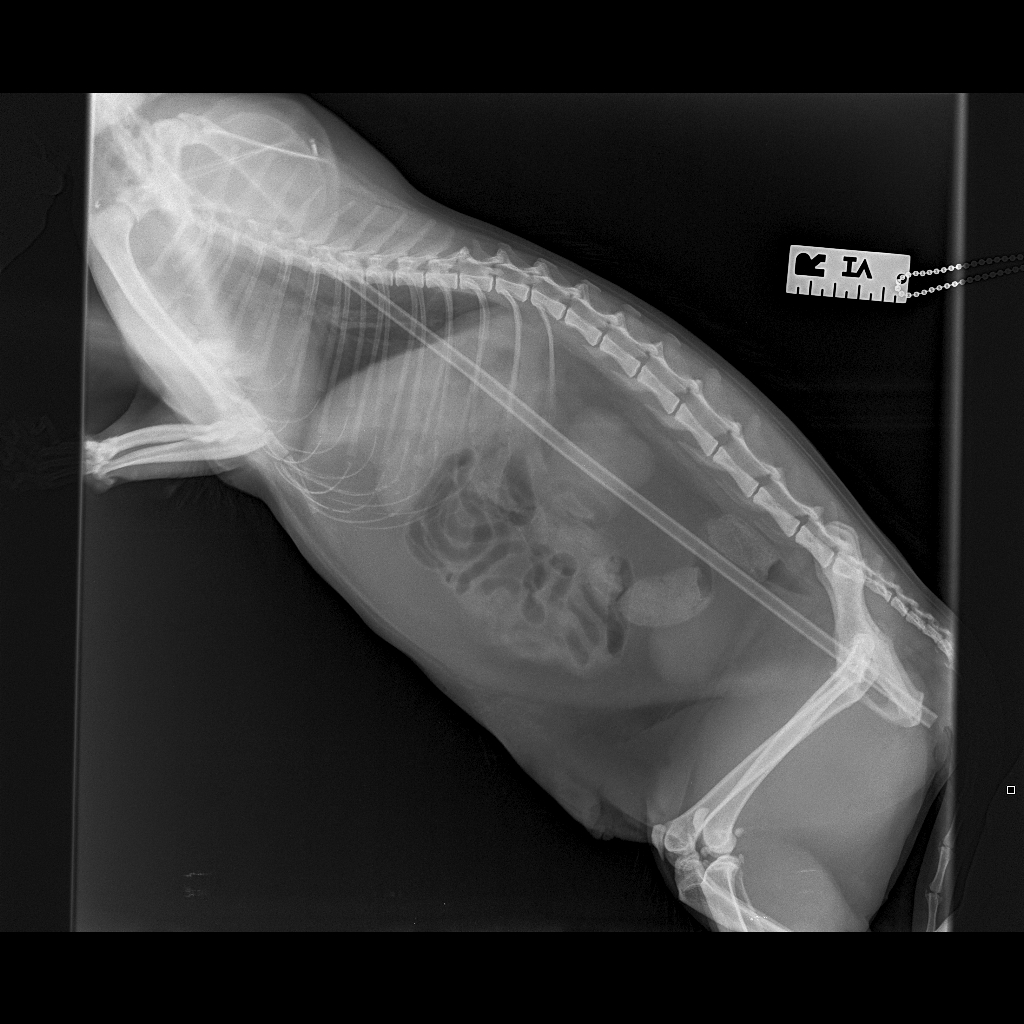

Alfold Vets practice manager Beth Tyrrell, who is a registered veterinary nurse, assisted with Salvador’s care and said they took X-rays and performed an ultrasound scan to find out what was going on inside the cat. The images showed there was a long, stick-shaped object extending all the way through her body, although it wasn’t clear exactly what it was.

“We were all completely astonished when we discovered that the stick was in fact a plastic plant support, which had gone in near her groin, then pushed up through her ribcage and into her chest. Miraculously, it had missed all of Salvador’s vital organs, including her heart, lungs and liver.

“The surgery took a couple of hours as Malwina needed to work very carefully to remove the stick and had to cut it in half because of the plastic caps on each end. While these could have helped save Salvador’s life when she had the accident by helping the cane glide through her body and past her organs, they were stopping us pulling the stick back out through the ribs.